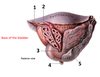

1? 2?

5? 6? 7?